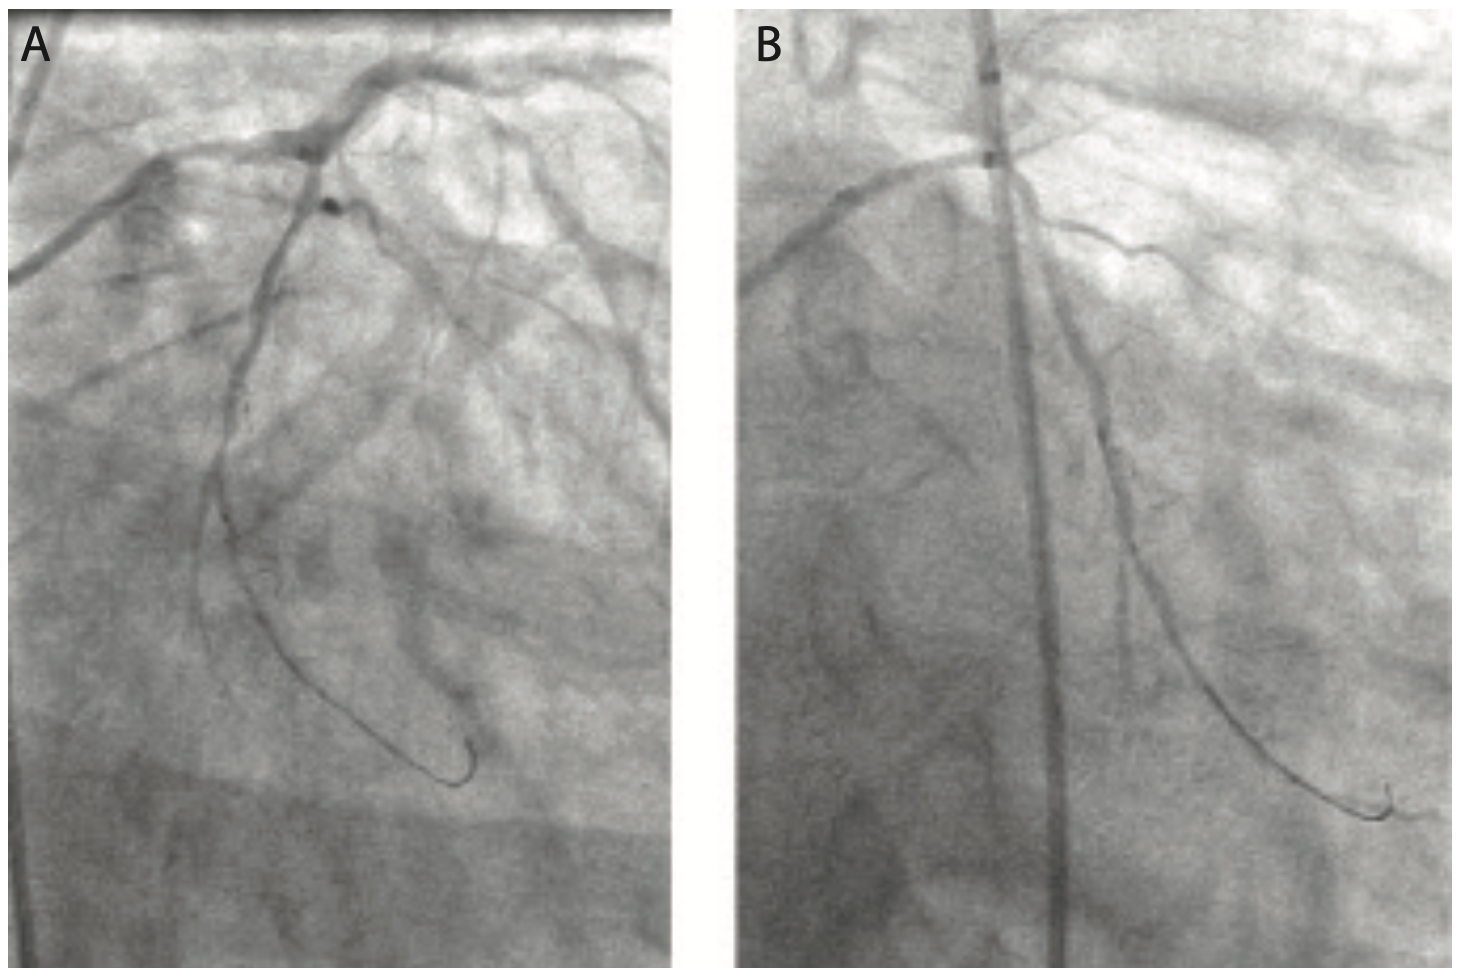

Figure 4 and Video 2A and Video 2B show the LCx in antero-posterior (AP) caudal and right anterior oblique (RAO) caudal projections. Due to the cumulative 290° angle between the takeoff of the proximal LM segment and the direction of the LCx artery, it was not possible to advance a wire past the proximal LCx artery segment. Four different wires were used (Sion Blue [Asahi Intecc], Whisper extra support [ES] [Abbott Vascular], Choice Extra Support [Boston Scientific], and Whisper medium support [MS] [Abbott Vascular]) without successfully passing beyond the proximal LCx segment, due to recurrent wire prolapse back into the ramus branch once the wires made the turn into the mid LCx segment. The friction caused by the LCx angulation eliminated the transmission of torque to the tip of the wire despite the use of polymer-jacketed and hydrophilic wires (Figure 5 and Video 3). We did not think that advancing an over-the-wire low-profile balloon or straight microcatheter would help in this situation, because there was not enough wire purchase into the vessel to advance these devices without a recurrent wire prolapse.

At this point, the device used to wire the vessel successfully was a SuperCross 120° angulated coronary microcatheter (Teleflex) (Figure 6). In order to effectively wire the angulated LCx without the risk of subintimal wire passage, the SuperCross 120° was advanced over the wire into the ramus branch, then pulled back to the distal LM at the site of the visualized takeoff of the LCx. The Whisper MS wire was pulled back to the tip of the microcatheter and then advanced into the LCx artery. The OM3 branch was wired with excellent torque transmission to the tip of the wire through the dedicated microcatheter (Figure 7 and Video 4A and Video 4B). The Whisper MS wire was then exchanged for Choice ES wire through the SuperCross 120°, in order to improve the deliverability of a stent to the distal tight lesion.